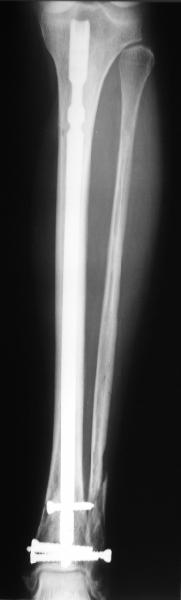

I am just trying to illustrate that prevention of 1)tibial valgus and 2)loss of reduction can be provided without fibular plating. Small changes of conventional nailing techniques allow to maintain reduction of the tibia reliably without adjunctive fibular stabilization.

In delayed cases acute length restoration performed only in the tibia may leave the fibula shortened thus change the mortise. So it is reasonable to restore length of both bones simultaneously by distractor and fix the fibula not with open reduction and plating but just by a single perQ screw. Example attached.